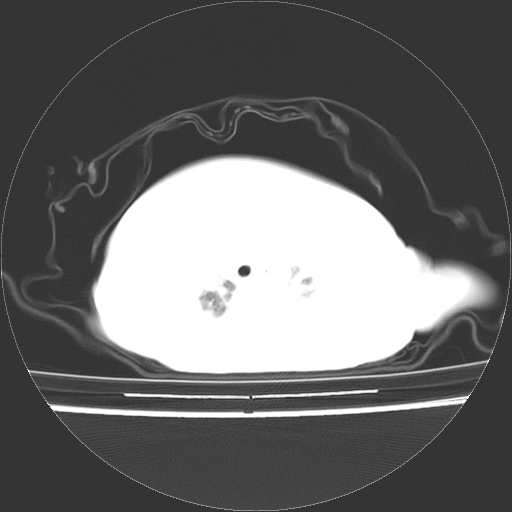

以下是引用影像之路在2009-5-8 15:46:00的发言:[br]1)胸廓畸形。2)考虑两肺感染性病变,并右肺上中叶肺不张;建议抗炎治疗后复查。3)胸腺肥大。4)前上中纵隔占位性病变待排;建议追踪复查。

以下是引用随光逐影在2009-5-8 8:33:00的发言:[br]1)胸廓畸形。2)考虑两肺感染性病变,并右肺上中叶肺不张;建议抗炎治疗后复查。3)胸腺肥大。4)前上中纵隔占位性病变待排;建议追踪复查。

以下是引用余辉在2009-5-8 8:44:00的发言:[br]鸡胸,胸腺肥大,双肺感染性病变,结合病史支原体肺炎可能性大